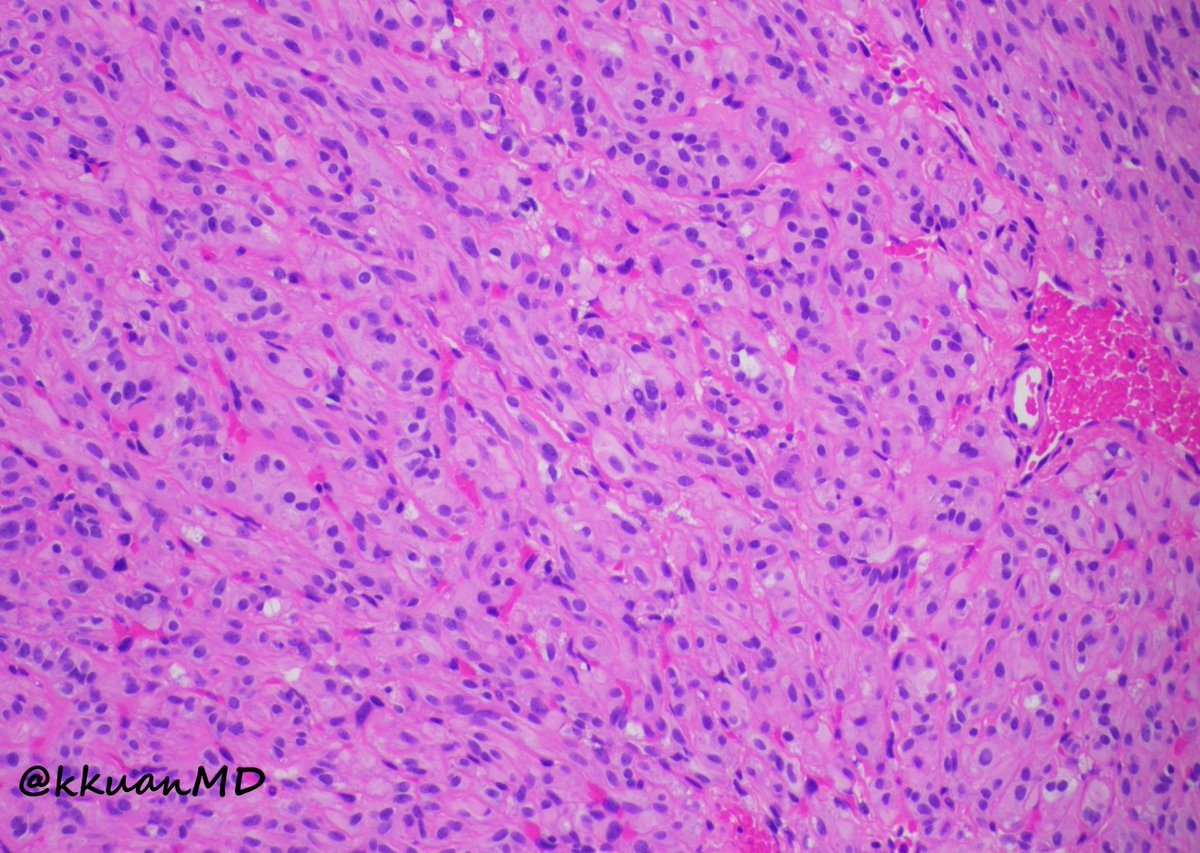

4 years

9

67

134